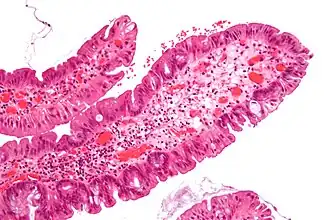

Polype adénomateux colorectal

Les polypes adénomateux colorectaux (ou adénomes colorectaux) sont des polypes qui se développent sur la muqueuse du côlon et qui comportent un risque élevé de cancer. Le polype adénomateux est considéré comme pré-malin, c'est-à-dire susceptible de se transformer en cancer du côlon. Les autres types de polypes qui peuvent apparaître dans le côlon sont les polypes hyperplasiques et inflammatoires. Ils sont peu susceptibles de se développer en cancer colorectal.

Environ 50 % des personnes âgées de 60 ans auront au moins un polype adénomateux de 1 cm de diamètre ou plus. Les polypes adénomateux sont souvent issus d'une polypose familiale ou d'une polypose adénomateuse familiale, un facteur qui entraîne un risque très élevé de cancer du côlon. Les adénomes représentent environ 10 % des polypes. La plupart des polypes (environ 90 %) sont de petite taille, généralement inférieure à 1 cm de diamètre, et ont un faible potentiel de malignité. Les 10 % restants sont des adénomes de plus de 1 cm qui ont 10 % de chances de contenir un cancer invasif.

En outre, la forme des polypes est liée au risque de progression vers un carcinome. Les polypes pédiculés sont généralement moins dangereux que les polypes sessiles. Les polypes sessiles ont une plus courte voie pour la migration des cellules invasives de la tumeur dans la muqueuse, et ils sont aussi plus difficiles à éliminer et à dépister. Les polypes sessiles de plus de 2 cm contiennent généralement des caractéristiques villeux, ils ont un potentiel plus élevé de malignité, et ont tendance à réapparaître après une polypectomie coloscopique.